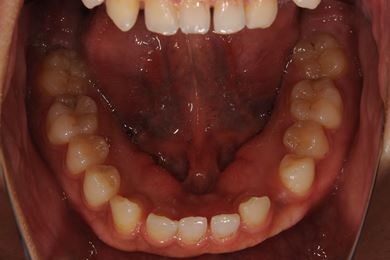

| 性別/年齢 | 女性 / 22歳 | ||||||||||||||||||||||||||||||||

| 主訴 | 前歯の隙間 | ||||||||||||||||||||||||||||||||

| 治療方針 | 舌が前に出てしまったり、左下の糸切り歯が一本足りないことで、上下の歯に隙間がある状態です。口元はきれいなので、非抜歯にて治療を開始しました。顎のずれがあるので、上下にゴムを使用しながら、また舌の練習をしながら治療しました。左下の欠損部にはデンタルインプラントで補綴し咬合させました。保定装置は隙間が出ないように上下とも裏から針金を装着しています。非抜歯治療で治療期間が1年半と予想していましたが、舌の癖があまり改善されなく、2年と治療期間が延びてしまいました。今後も舌が出ないように気を付けていただきます。保定装置の使用も初診時に説明し、診断時の治療計画にも記載していましたが、きちんと理解されていなかったようで、除去後保定装置の使用にショックを受けさせてしまいました。今後また改善していきたいと思います。頑張って咬合の維持をしていきましょう。 | ||||||||||||||||||||||||||||||||

| 治療内容 | 唇側矯正(ホワイト・非抜歯)、インプラント1本、メタルボンドセラミック1本 | ||||||||||||||||||||||||||||||||